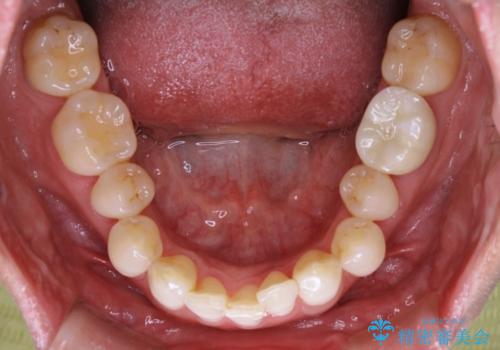

【抜歯】矯正治療とインプラントで正常な噛み合わせを実現

- 元々は矯正治療を主訴にご来院されました。

治療を始めるにあたり、精密検査を受けていただき全体の状況を把握したうえで矯正治療の計画を立てることとなりました。

その過程で左下の6番目の歯は治療が必要な状態であることが分かり、被せ物を外して内部を確認してみると根が破折してしまっていることが判明しました。

歯が深い位置で破折している場合は基本的には抜歯が選択されます。

様々な治療プランを患者さんと相談させて頂き、最終的にインプラントで噛み合わせを回復させていくこととなり、まず悪くなっている歯を抜歯することから開始しました。